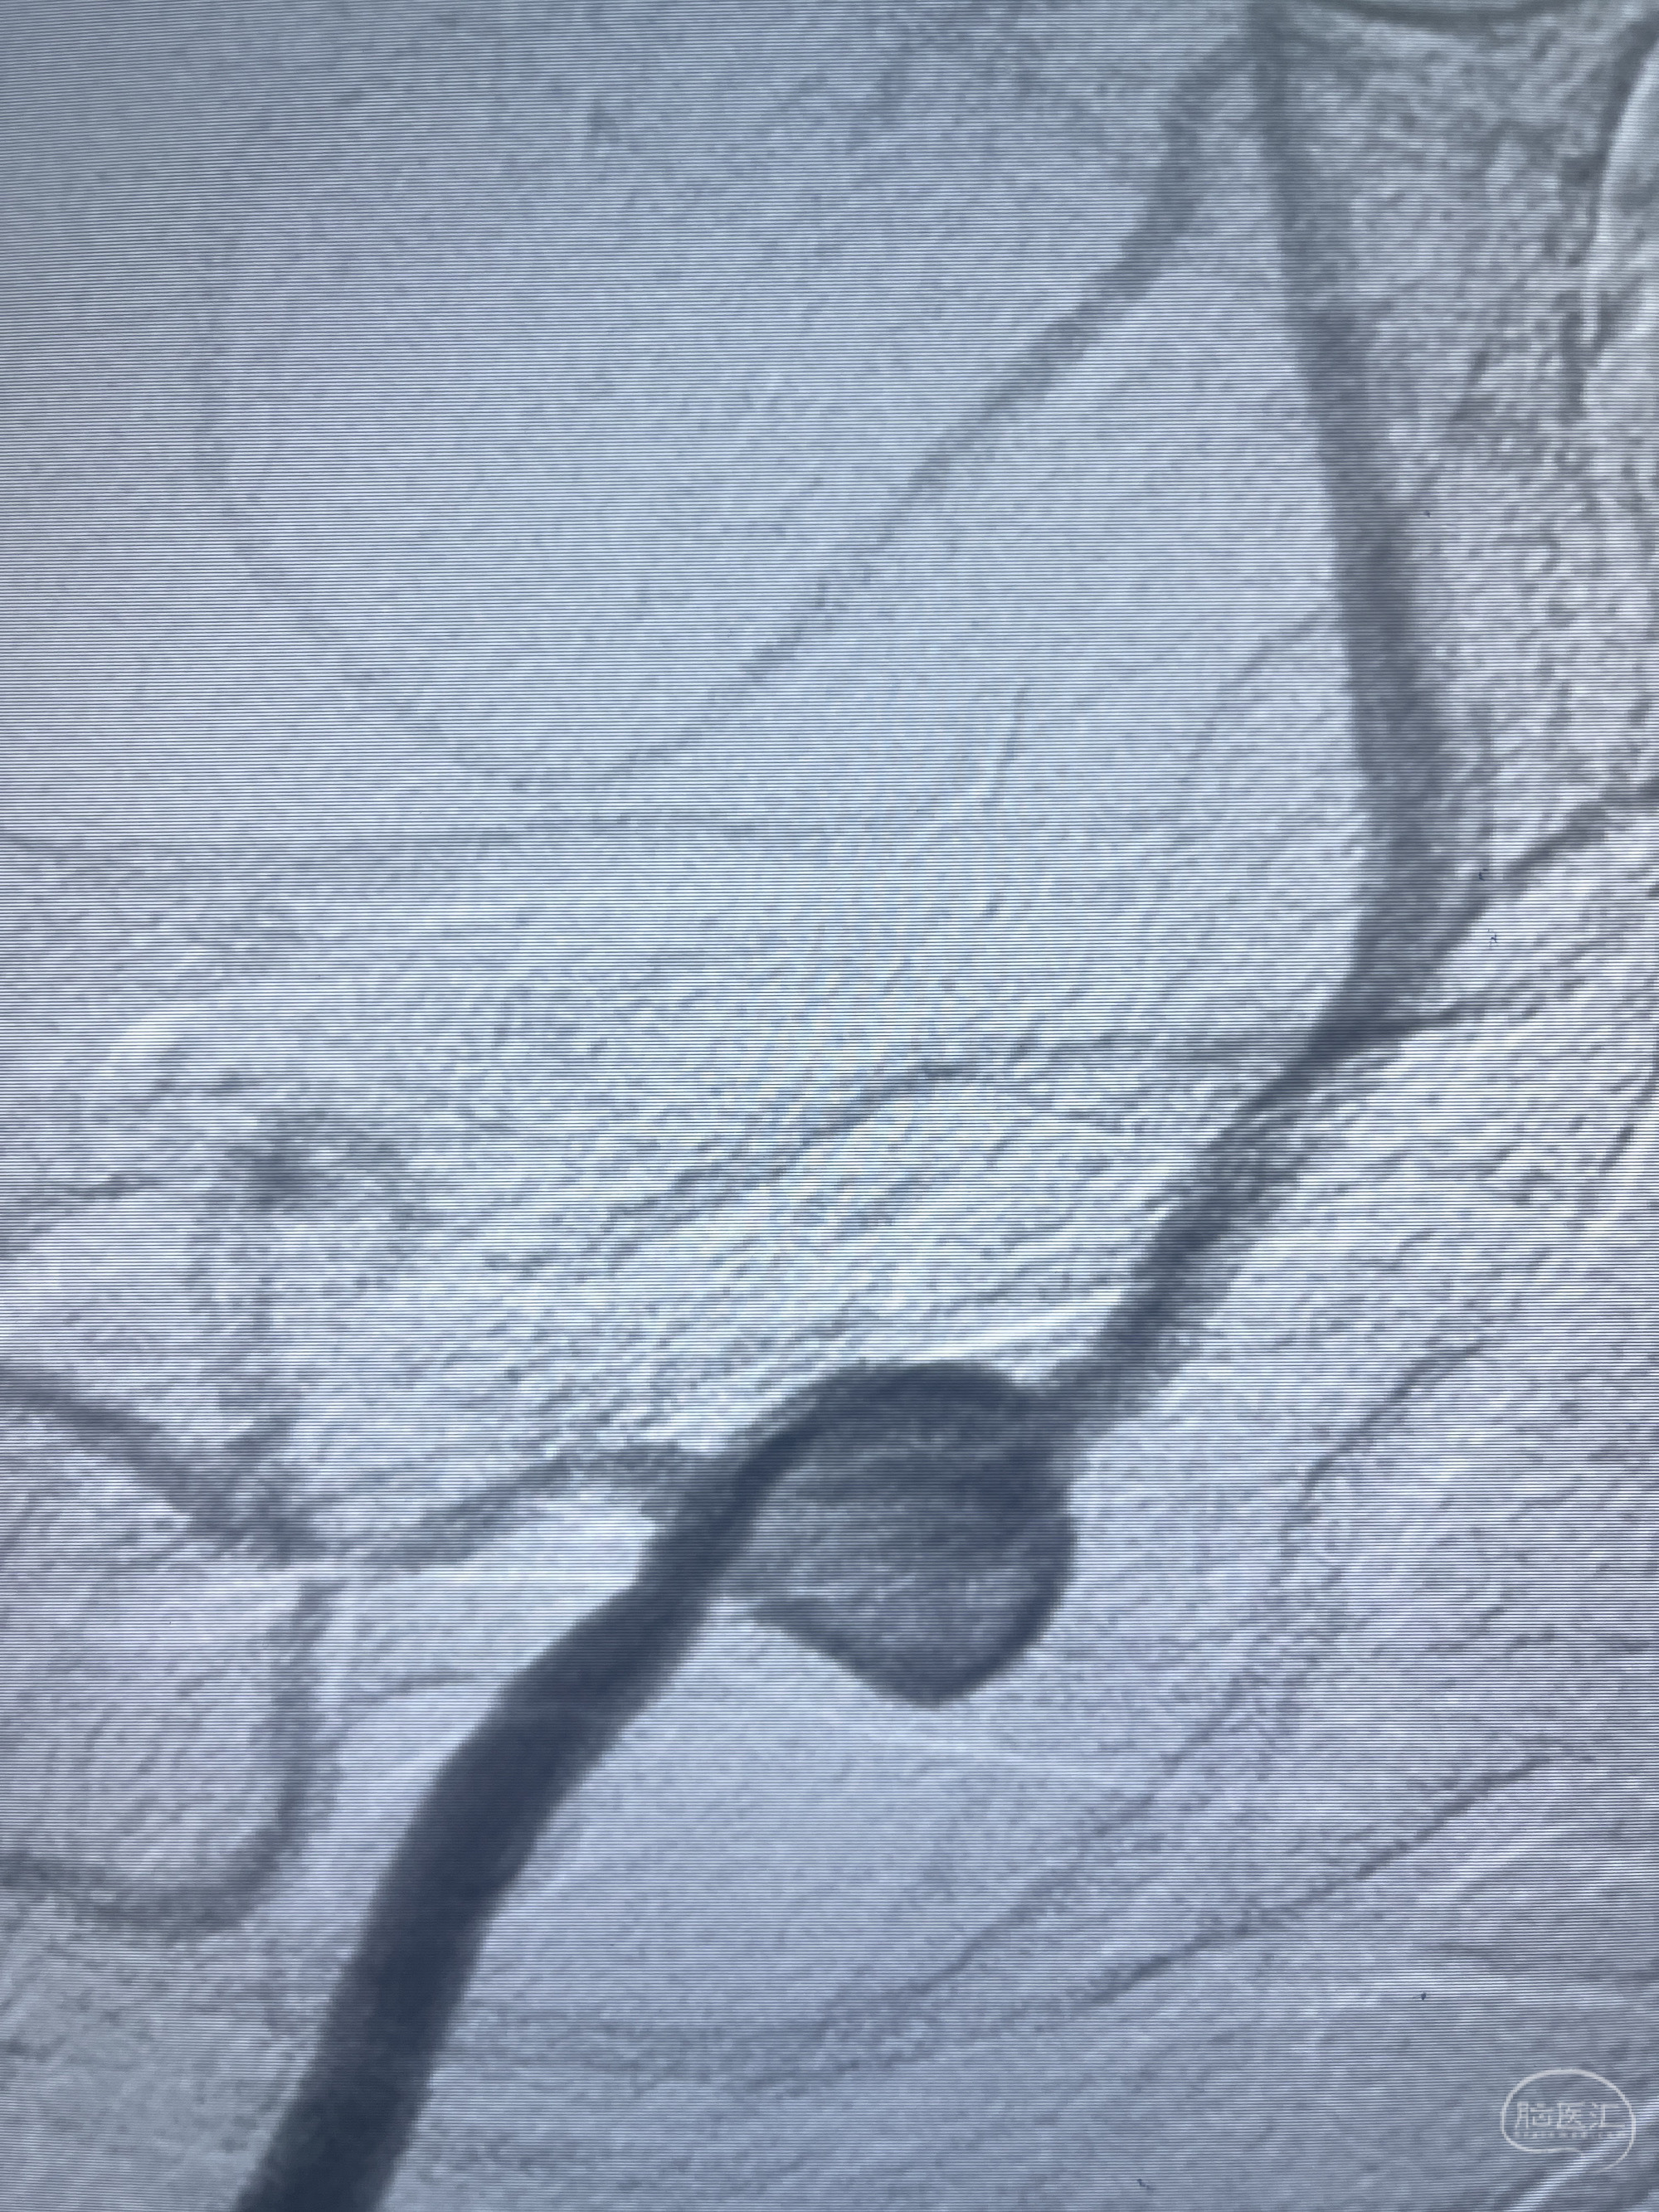

202.04.28脑血管造影:右侧大脑后动脉远段闭塞,右侧椎动脉V4段可见“囊状造影剂填充影”,大小7.64*7.65mm,可见PICA由动脉瘤发出;